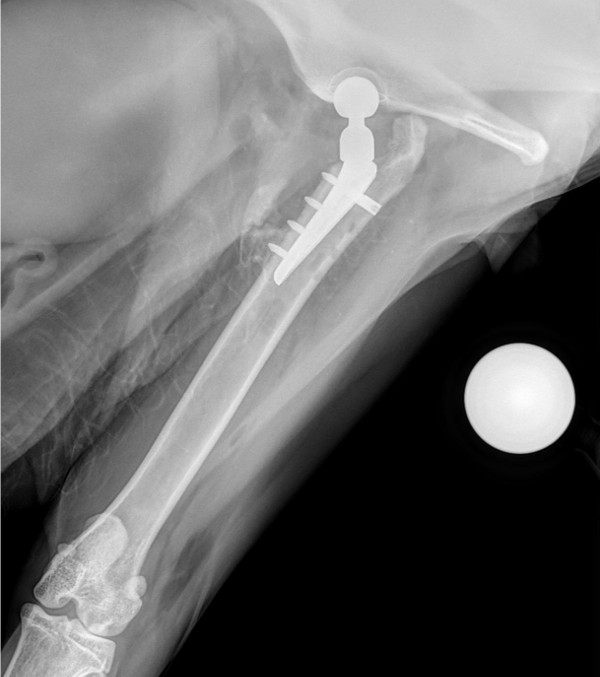

Figure 1

Figure 2